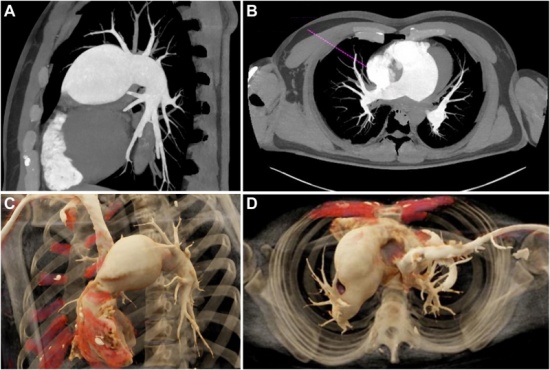

С най-голямо информативно значение са данните от образните методи на изследване, като диагнозата се основава на данните от рентгенографията на гръдния кош, ехокардиография, компютърна томография, ядрено-магнитен резонанс и други. Най-точният и широко използван метод е компютърната томография, която дава ясна представа за локализацията, формата и размерите на аневризмата, засягането на околните структури.

Заглавно изображение: https://doi.org/10.1016/j.atssr.2024.10.018, Under a Creative Commons license